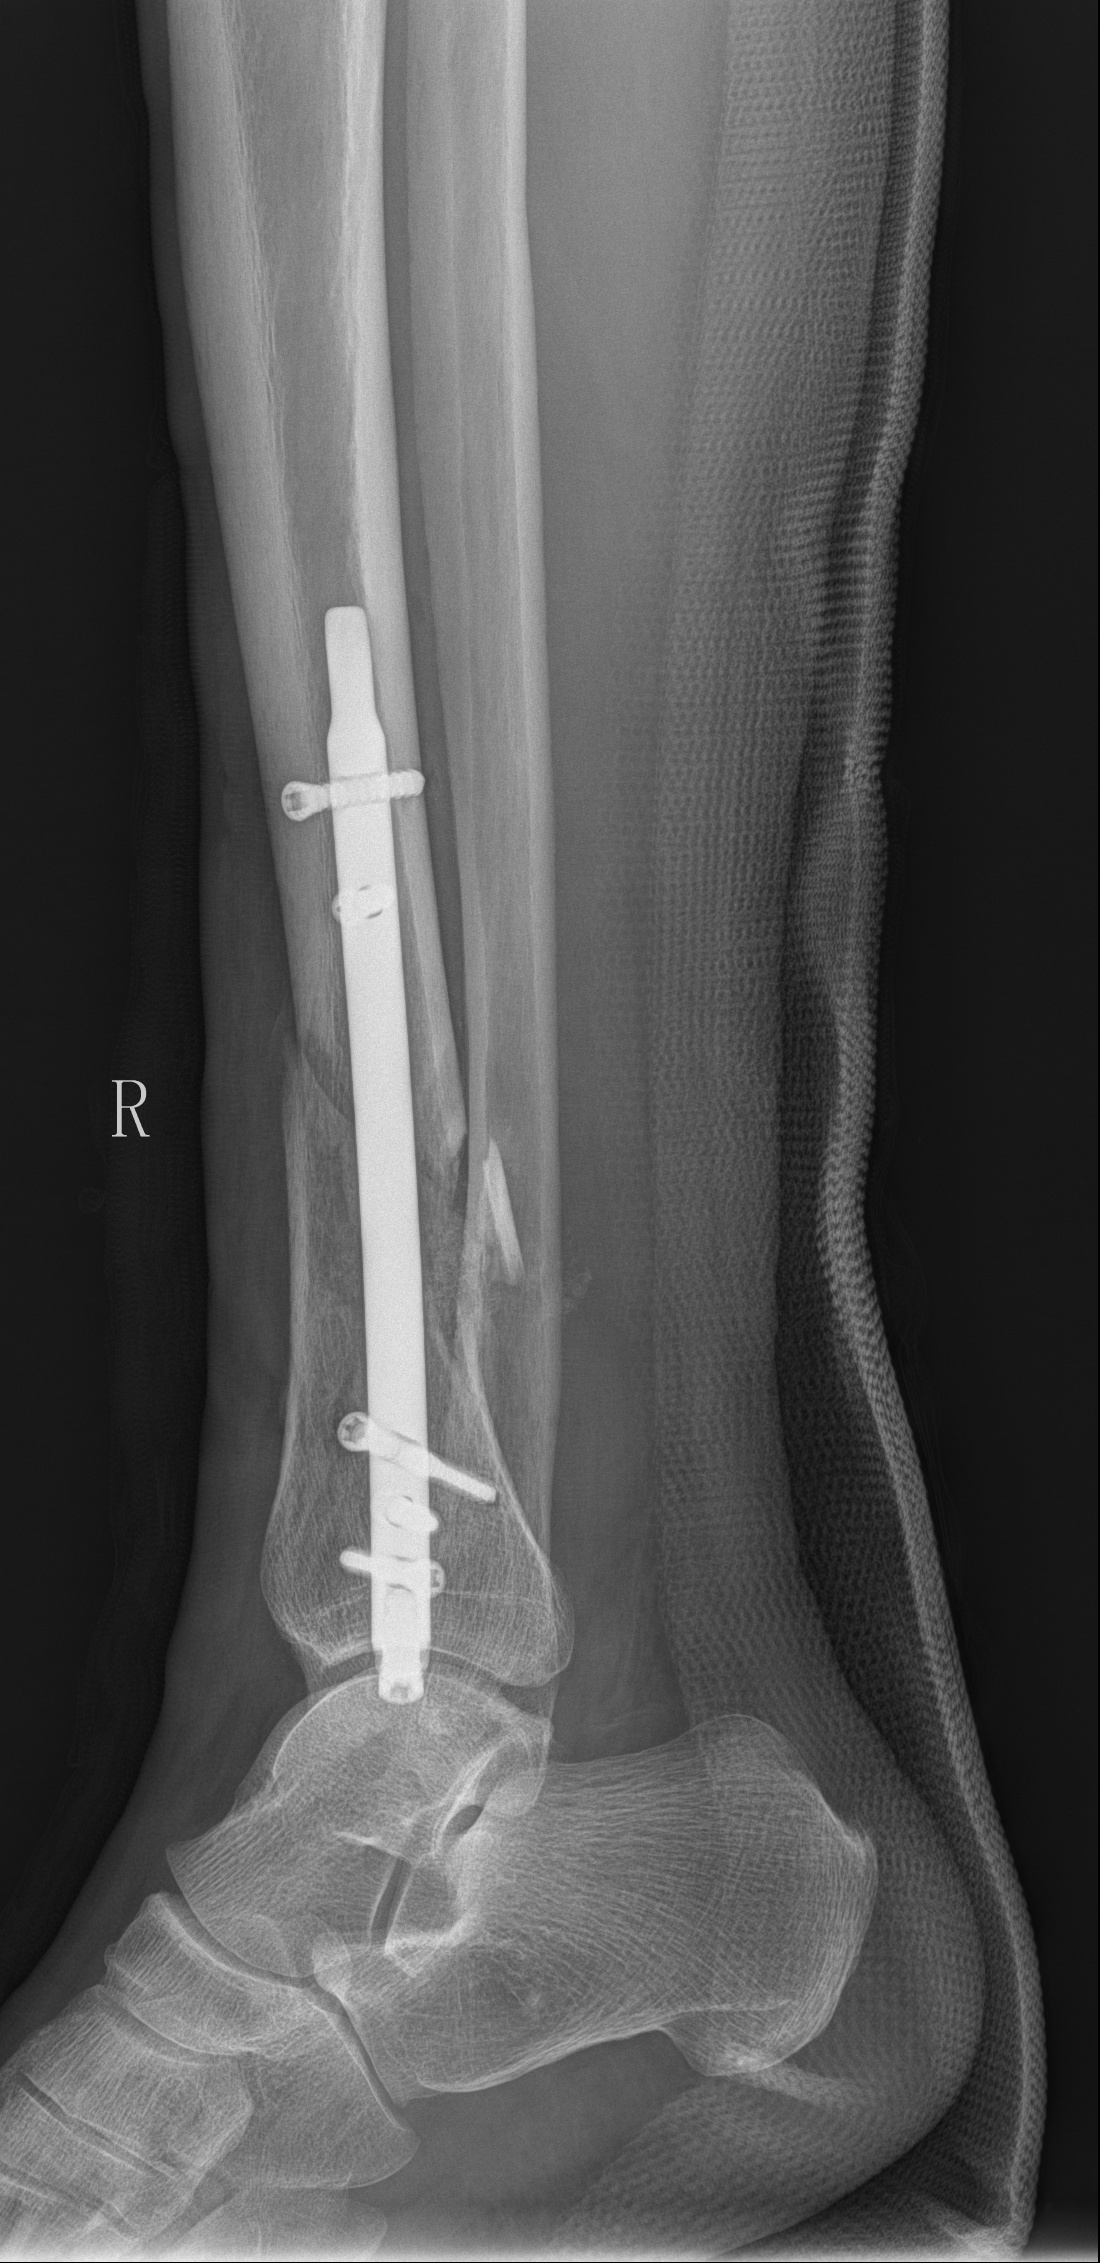

创伤骨科以中西医结合诊治四肢骨关节创伤为主要临床任务和研究方向。为患者提供最恰当的治疗方案和方法。应用传统的闭合手法复位小夹板固定技术、中西医结合内、外固定技术和现代生物学固定理念微创技术治疗四肢、骨盆及关节的各类新鲜、陈旧的复杂难治性骨折。注重中医中药三期辨证施治(内服外用)在骨折治疗中的应用。目前,我科在陈旧性骨盆骨折、髋臼骨折属省内领先,使用Ilizarow技术及外固定支架治疗开放性骨折,慢性骨髓炎、骨折不愈合,创伤引起的肢体畸形,在软组织修复方面有独特经验。近年来,我科在省内率先开展了系列微创手术治疗各种骨折,尤其是老年髋部骨折(PFNA),使用该方法后,术后1周可扶拐行走,明显减少了各种长期卧床并发症,提高了生活质量,取得了良好的社会效益。

3.股骨近端防旋髓内钉(PFNA)治疗老年脆性粗隆间骨折